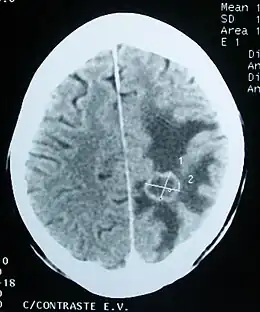

Œdème (zones sombres) autour d'une tumeur cérébrale secondaire.